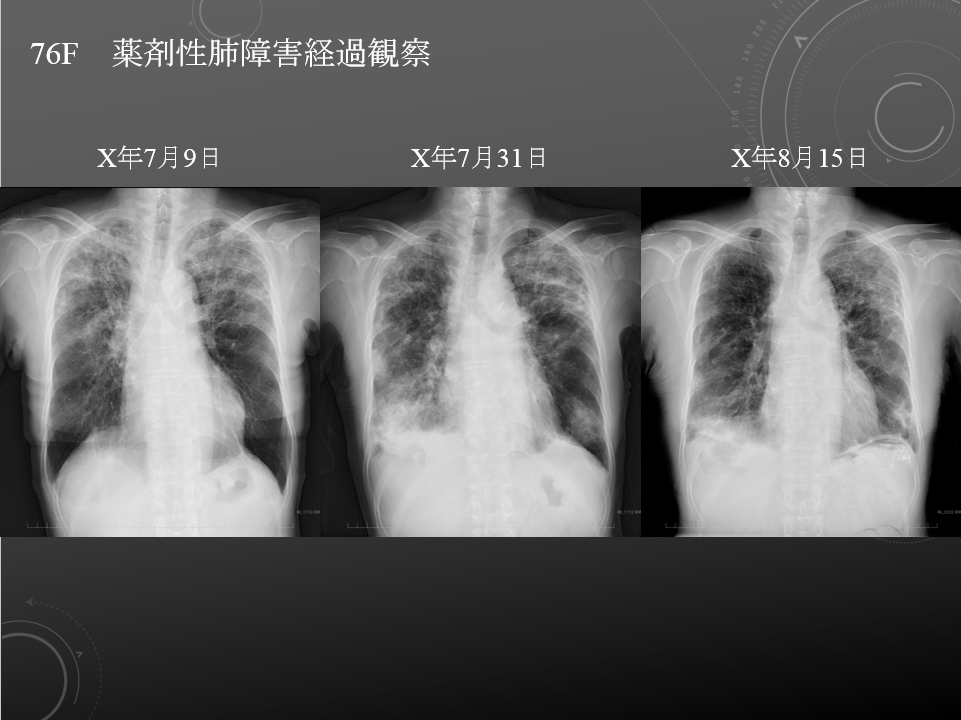

すべて立位 7月31日は胸水もあり 縮みも